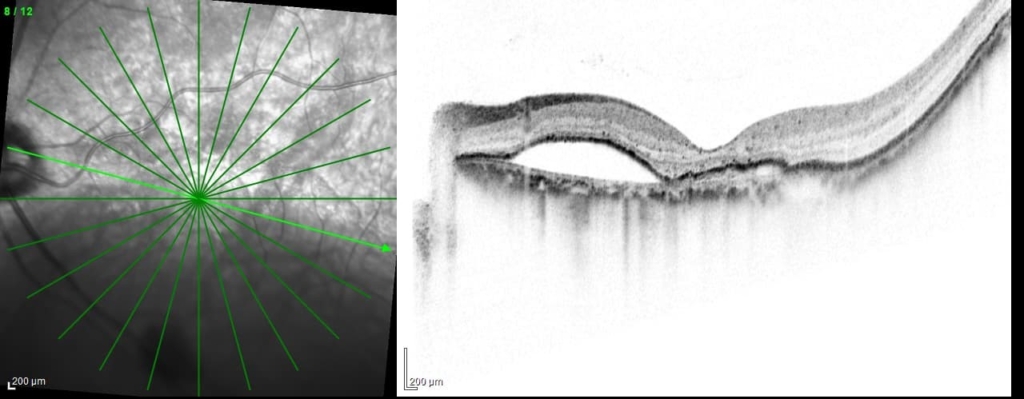

乳頭が下鼻側に傾斜し、下方に萎縮(PPA)がみられる。

両眼ともに、後部ぶどう腫staphylomaの上縁に一致して乳頭下縁から黄斑を横断するように帯状の網脈絡膜の萎縮巣がみられる。また後部ぶどう腫領域に一致して網膜・脈絡膜が菲薄化しているため、紋理眼底tessel lated fundusがみられる。

後部ぶどう腫の上縁に漿液性網膜剥離(SRD)がみられる。この後部ぶどう腫と正常部の境界付近に脈絡膜新生血管の発生を見ることもあるため、注意が必要。